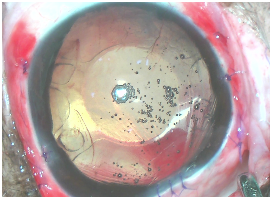

세극등 검사를 통한 수정체 위치 이상 확인

울산 강아지 수정체 탈구 후안방 관찰 / 출처: 에스동물메디컬센터

세극등 검사에서 각막과 수정체가 가까워짐 / 출처: 에스동물메디컬센터

1️⃣ 수정체 표면 염색

3mm 각막 절개 후 트리판 블루(Trypan Blue) 염색약을 사용해 수정체 표면을 염색했습니다. 이를 통해 시야를 확보하고 절개선의 정확도를 높였습니다.

트리판 블루 염색 사진 / 출처: 에스동물메디컬센터